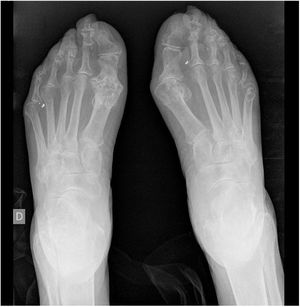

She visited our surgery due to arthralgia in the hands and feet with a crisis of pain and functional impotency in multiple joints that has evolved over more than 15 years. Physical examination found major tophaceous deposits in the hands and feet, most strikingly in the right hand (Fig. 1), with incapacity of grasping, above all in the right hand.

Bone X-ray imaging showed an important increase in the soft parts, with trapping and erosion in the metacarpophalangeal, proximal and distal interphalangeal joints of both hands (Fig. 2), as well as erosion on the first metatarsal joints and luxation of the 5th left metatarsal joint (Fig. 3).